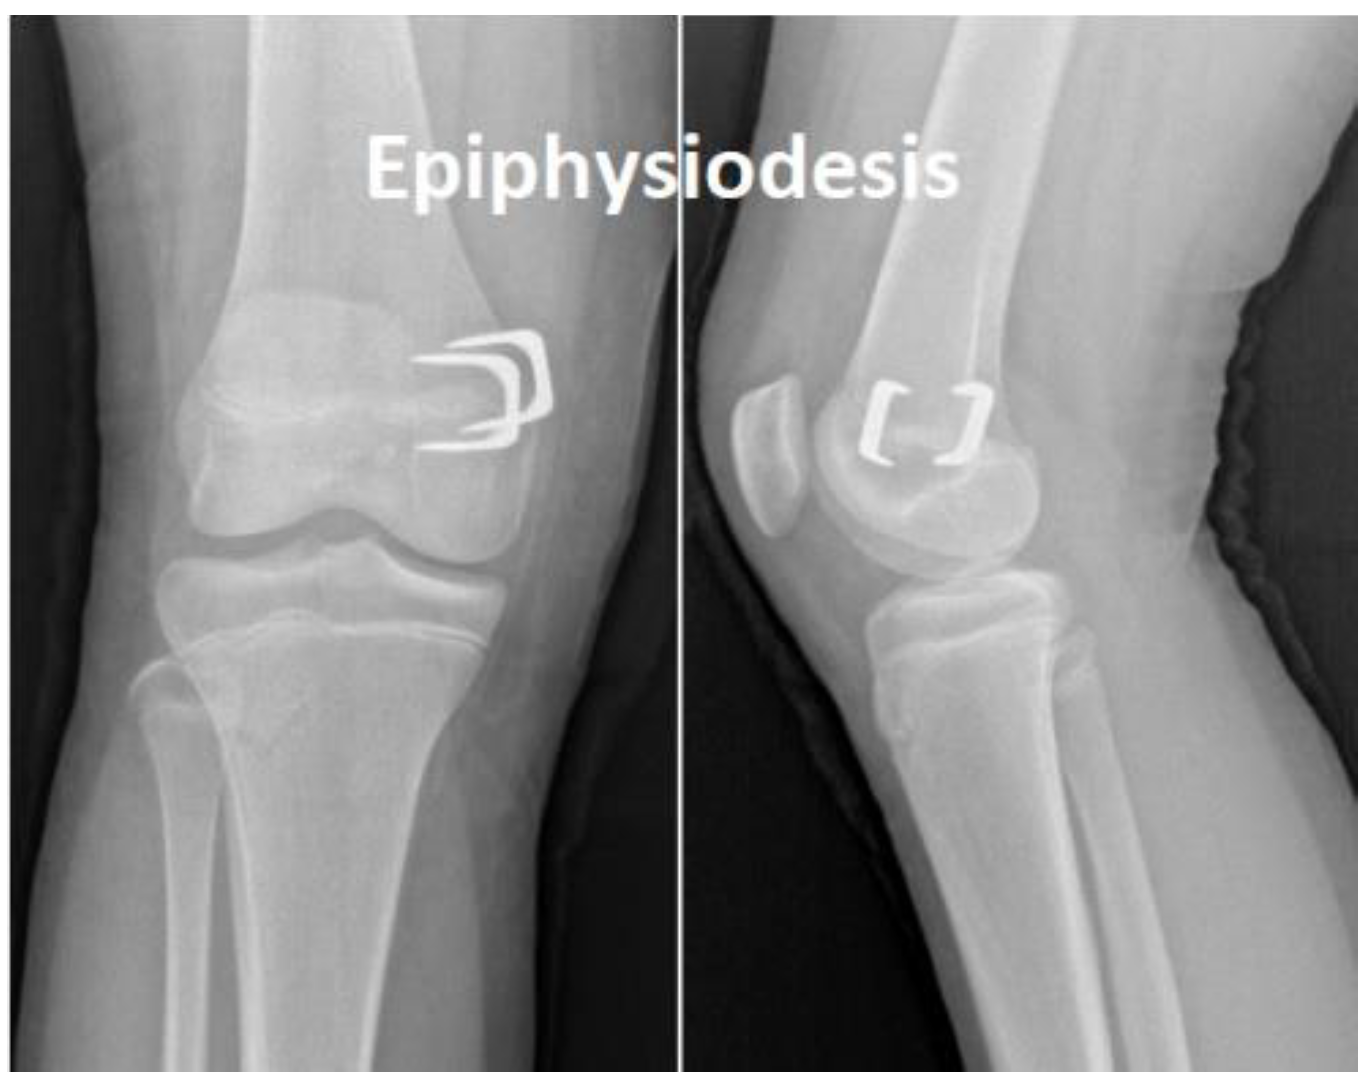

Using staples, the physis (epiphyseal plate) can be relatively simply restrained either on both sides when correcting limb length discrepancy (i.e., “epiphysiodesis”) or only on one side when correcting angular deformities (i.e., “hemiepiphyseodesis”) (see Figure 1 and Figure 2). Unlike the irreversible method of permanent epiphysiodesis, see [8], epiphyseal stapling does not destroy the epiphyseal plate and, therefore, allows resumption of the growth once the optimal correction is achieved; see [4].

According to [1,4], besides accurate diagnosis confirmed by a radiogram of the whole limb (see Figure 2), good timing of the treatment is also very important. The surgical procedure involves a short longitudinal incision through soft tissues over the physis and extraperiosteal implantation of the staple using a special instrument under radiography control [11] (see Figure 3). The staple must bridge the physis but not penetrate it to prevent its impairment (see Figure 4).

Figure 1. Parts of the growing bone (tibia).

Figure 4. Position of staples bridging the physis in femur.